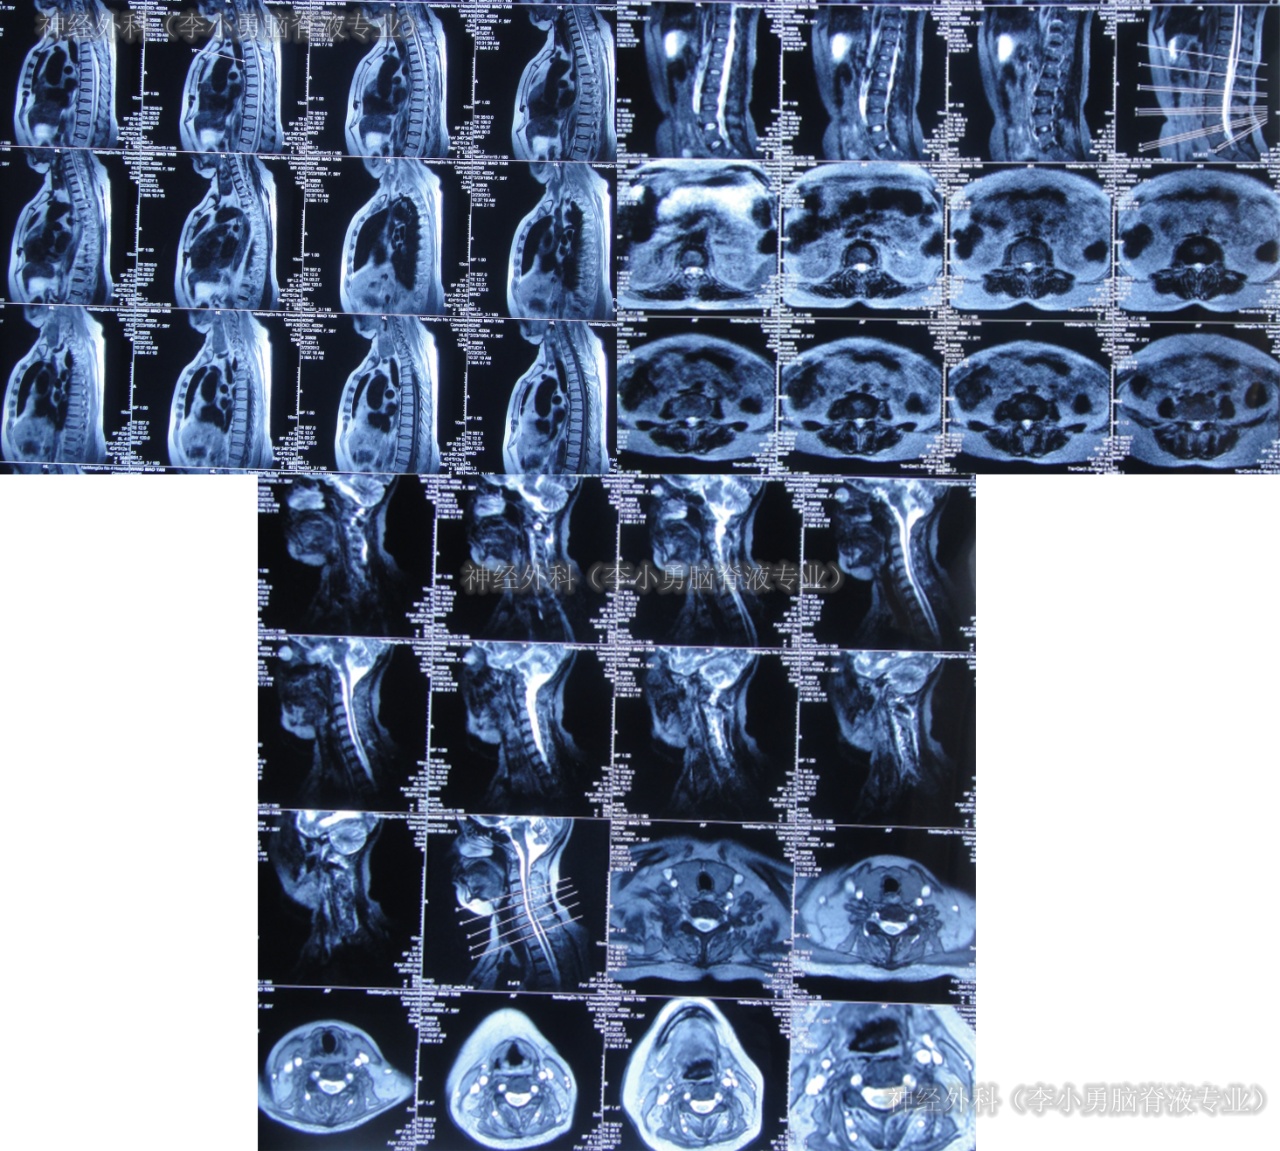

第2家医院出院1月余即2012年2月7日,夜里起夜突然又重复发作以前的症状(恶心呕吐、头昏),且比前2次发作严重,2012年2月8日住入第3家医院:呼和浩特市某三甲医院的神经外科治疗,入院查头颅CT(图-2)和MRI(图-3);脊髓核磁(图-4);肺部CT(图-5)及多次腰椎穿刺脑脊液化验检查(糖低、蛋白高),诊断为:结核性脑膜炎,脑积水。

图-4:2012年2月9日脊髓核磁